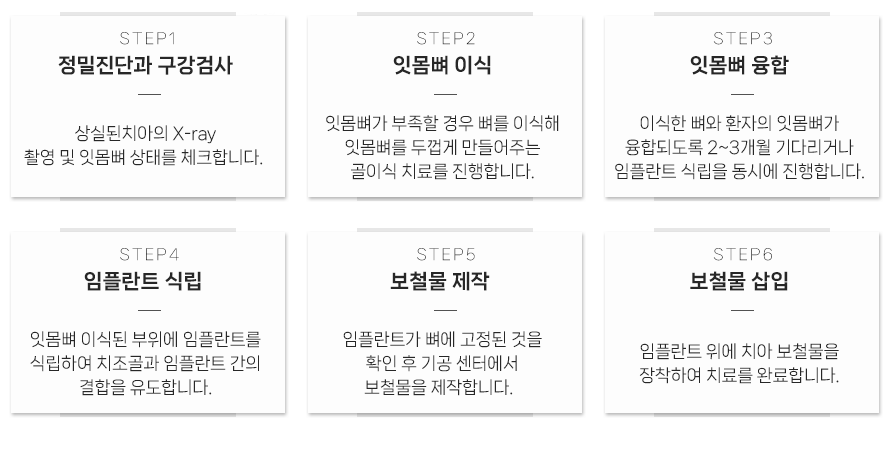

임플란트 주위를 둘러싼

뼈가 튼튼해야

임플란트가 튼튼하게 고정되어 오랫동안 안정적으로 사용할 수 있습니다.